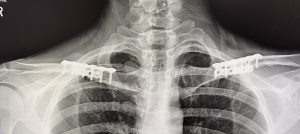

Radiographs often cannot clearly show the osteotomy line due to hardware density and the narrow end-to-end interface. The most definitive assessment of union typically occurs during later hardware removal when indicated. Hardware prominence may develop in patients with minimal soft-tissue coverage and is most often addressed 9–12 months post-operatively, once consolidation is complete.

- Typical bony ingrowth into the screw threads—especially within the superior 3.5 mm plate—was observed.

- Examination of the osteotomy sites showed a barely perceptible line with complete, solid bridging bone, consistent with primary bone healing.